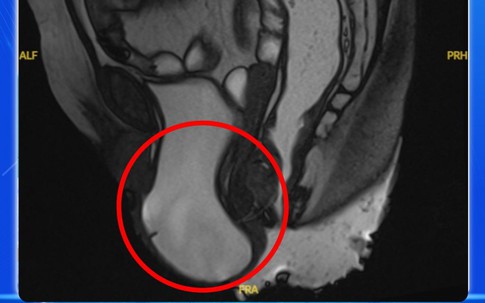

Mẹ và béGĐXH - Người phụ nữ bị sa sàn chậu có biểu hiện rối loạn tiểu tiện như tiểu khó, tiểu phải rặn và đôi lúc tiểu són, khiến cuộc sống thêm phần nặng nề...